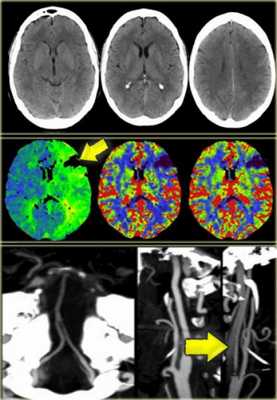

На нижележащих изображениях слева представлена диффузно-взвешенное изображение, на котором возможно выявить ишемизированную ткань. Среднее изображение соответствует мр- перфузии, на котором визуализируется огромная область гипоперфузии. На крайне правом изображении diffusion-perfusion mismatch визуализируется зона ткани-риска, которая отмечена синим и возможно будет сохранена после терапии.

Ниже представлены изображения пациента, у которого были установлены неврологические проявления около часа назад. Постарайтесь выявить патологические изменения, а после продолжите чтение.

Данные изображения соответствуют норме, поэтому следует перейти к диффузно-взвешенному изображению. Взгляните на следующие изображения.

На DWI выявляется зона ограничения диффузии, и если после выполнения перфузии не будет выявляться зона перфузии, то следовательно нет смысла выполнять тромболизис.

На выше лежащих изображениях визуализируется инфаркт в бассейне СМА. На КТ четко визуализируются необратимые изменения. Далее представлены DWI и перфузия. При сопоставлении зон становится ясно, что не нужно выполнять тромболизис

При ознакомлении с перфузионными изображениями, то визуализируется несоответствие. В левом полушарии выявлена область гипоперфузии. Данный пациент абсолютный кандидат на тромболитическую терапию.